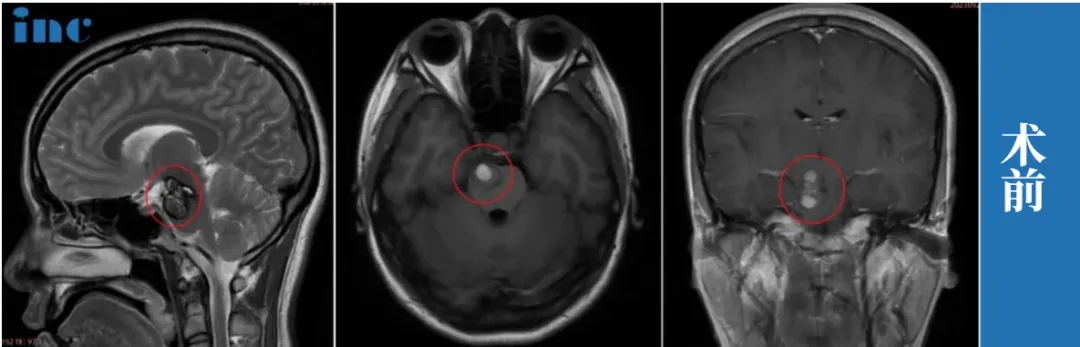

萱萱30岁、中脑-桥脑海绵状血管瘤

那天萱萱突然觉得头晕,站着时像踩在棉花上,右眼还偶尔发黑。和丈夫一起前往医院做检查,医生的诊断结果令这对夫妻眼前一黑:“中脑及桥脑右侧占位海绵状血管瘤继发出血。”

最终,萱萱决定找巴教授为其主刀切除这个脑袋里的“麻烦”。在巴教授中国行示范手术期间为萱萱顺利全切近20mm的脑干深处病变,术后无瘫痪、无视神经损伤、无呼吸抑制和昏迷风险,术后萱萱的恢复状况也很好。